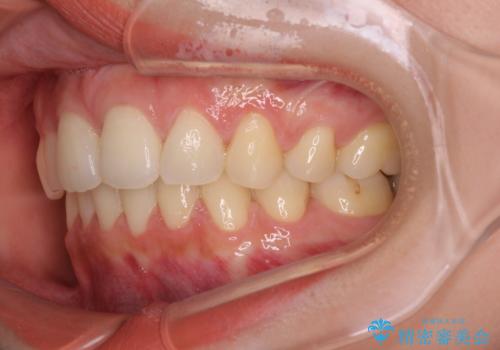

目立たない裏側装置 ハーフリンガルの抜歯矯正

上下左右の第一小臼歯4本を抜歯して口元を下げる治療計画としました。

3年半ほどで終わる予定でしたが、途中引っ越し、出産、引っ越し、出産を繰り返し、なかなか来院することができず、装置を外すまでに8年以上の期間がかかってしまいました。